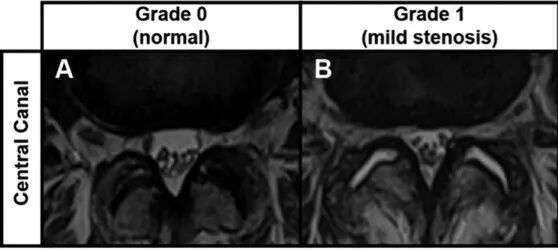

中央管 (CC) 狭窄等级实例:(A) 0 级(正常)CC 狭窄,无蛛网膜下腔闭塞。(B) I 级(轻度)CC 狭窄伴蛛网膜下腔闭塞,但马尾神经明显分离。(C) II 级(中度)CC 狭窄伴有蛛网膜下腔显著闭塞和马尾部分聚集。(D) III 级(严重)CC 狭窄伴蛛网膜下腔完全闭塞;马尾的细根无法区分。